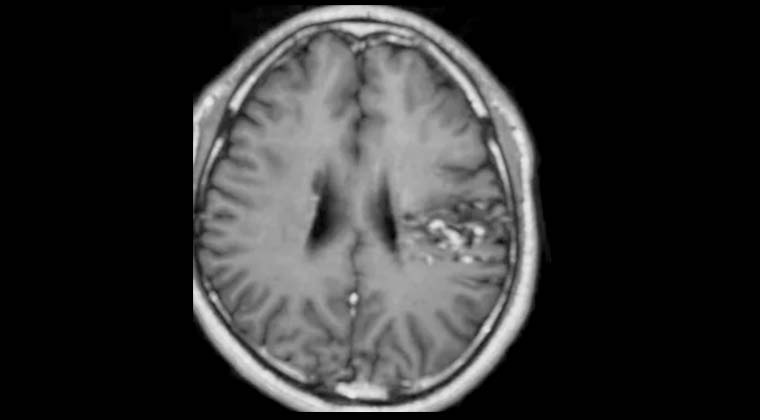

Рисунок 3: 25.07.2022, через 5 месяцев после лечения контрольное МРТ показало, что опухоль в правой лобной доле исчезла, пациентка ходит самостоятельно.

Рисунок 4: 25.07.2022, контрольная МРТ показывает, что опухоль в левой височной доле также исчезла.